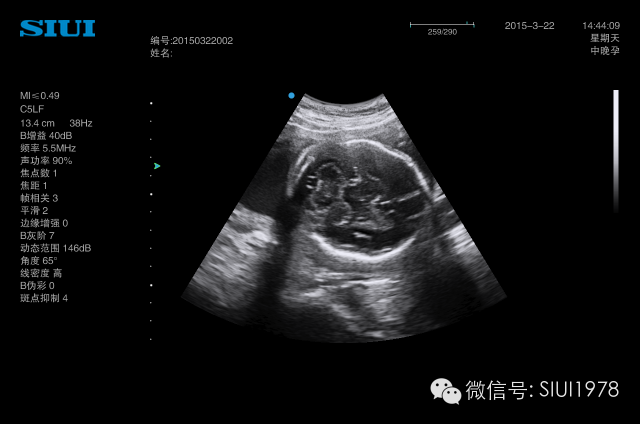

近年来超声医学的发展日新月异,彩色多普勒、三维超声、四维超声等新技术广泛应用。在妇产科领域,产前超声诊断的需求显著增加。由于兼有无创、便捷、价廉、实时、动态等优点,超声检查已成为目前临床上筛查胎儿发育畸形中最常用的影像学手段。

近年来,颜面部结构的辨认与颜面部畸形的产前超声诊断越来越受到人们的重视,三维超声的飞速发展,能将颜面部结构及畸形非常逼真地展现在人们面前。随着超声仪器的不断发展,图像分辨力的不断提高,颜面部的许多细小结构及某些面部表情亦能清晰可辨,如胎儿人中的显示,胎儿争眼、皱额等细微表情动作的显示与观察等。眼眶、眼球、眼裂、眼睑、前额、鼻、鼻骨、上下唇、人中、上颌骨及上牙槽突与其内的牙胚、下颌骨及下牙槽突与其内的牙胚、下颌、硬腭、舌、口、颧骨、耳廊等结构均能清晰可辨,因此,对这些正常结构的正确认识,对提高颜面部结构畸形的认识是非常有帮助的。